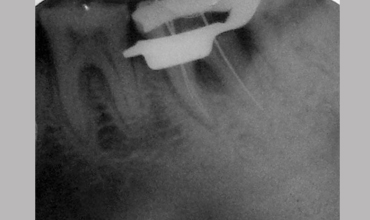

NON SURGICAL MANAGEMENT OF ENDODONTIC LESION AND SURGICAL MANAGEMENT OF PERIODONTIC LESION